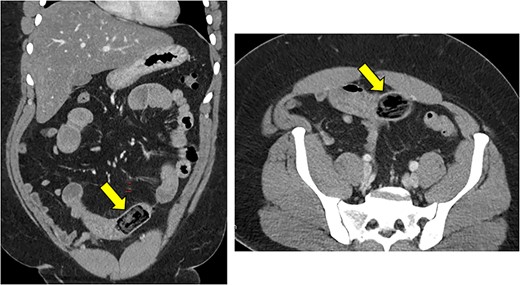

Abdominal CT scan demonstrated small bowel obstruction with loops of small bowel in the central abdomen measuring up to 3.4 cm in diameter. A transition point was noted in the distal small bowel with a rectangular object, which appeared to be an ingested foreign object (Fig. 1).

Dilated small bowel with a transition point in the distal small bowel with a rectangular object, which appeared to be an ingested foreign object.